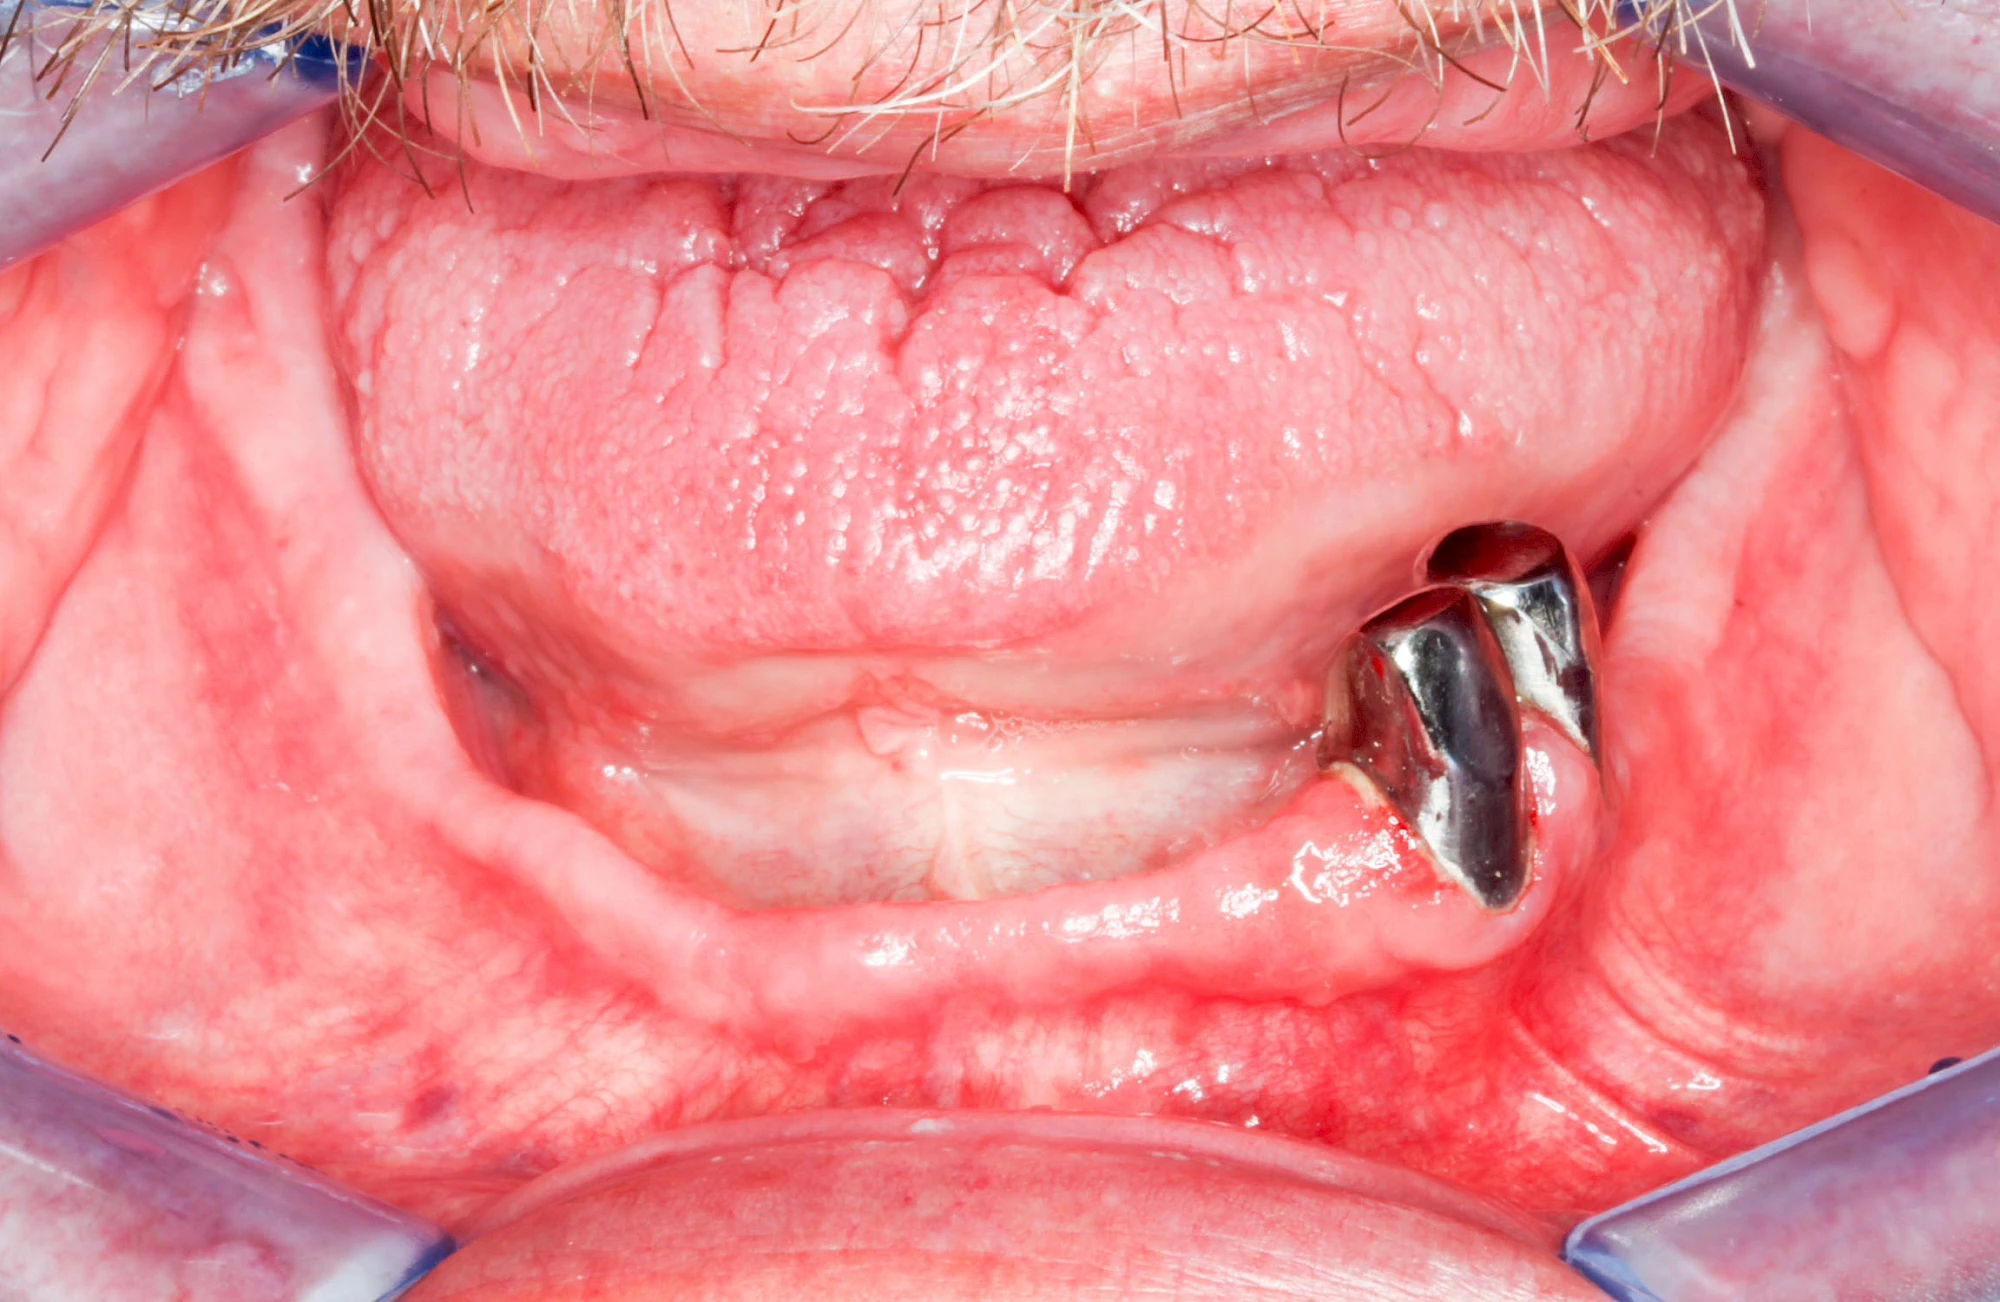

Knochenschwund (Atrophie)

Gehen die Zähne verloren, baut häufig auch der Kieferknochen ab (Knochenschwund). Die Geschwindigkeit und das Ausmaß des Knochenschwundes ist von vielen Faktoren abhängig. Neben der genetischen Veranlagung spielen auch Überbelastungen in Folge, z. B. bei ständigem Knirschen oder Pressen, eine Rolle. Auch wenn Zahnprothesen Tag und Nacht getragen werden, kann die ständige Belastung der Schleimhäute und des Knochens den Knochenschwund beschleunigen.

In seltenen Fällen schwindet nur der Knochen, aber nicht die bedeckenden Schleimhäute. In diesen Fällen spricht man von einem sogenannten "Schlotterkamm".